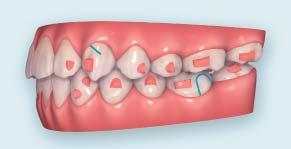

Fig. 1 Fig. 2 Fig. 3 Fig. 4

Figs. 1-8: Intra and extra oral images before treatment Fig. 9: Panoramic radiograph before treatment Fig. 10: Cephalometric radiograph before treatment Fig. 10

Fig. 11 Fig. 12 Fig. 13 Fig. 14 Fig. 15

Figs. 11-15: Initial ClinCheck treatment plan

Figs. 26-30: Final ClinCheck treatment plan